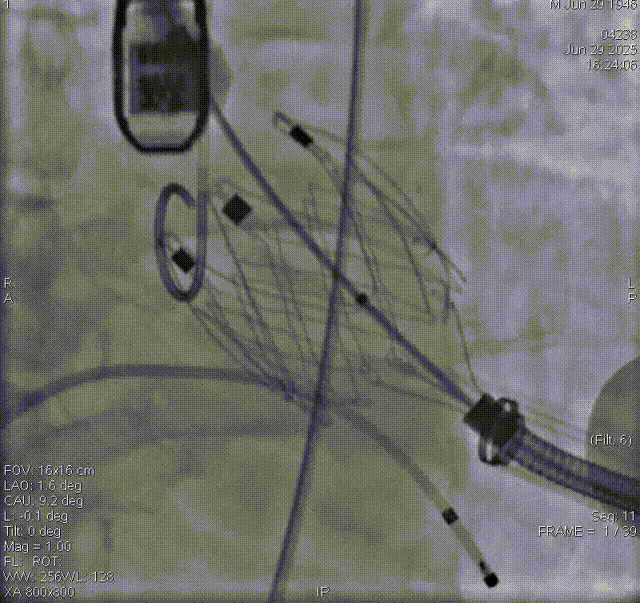

术前评估

术前影像评估提示,患者为典型三叶瓣结构,瓣窦分布均匀,无明显钙化,主动脉瓣环直径29.3mm,左室流出道直径30.6mm,STJ直径37.8mm,升主动脉直径40.5mm,双侧冠脉开口高度充足(左冠17.0mm,右冠27.6mm),无冠脉阻塞风险,左室-主动脉夹角137°,存在一定同轴性挑战。

CTA评估(上下滑动查看更多照片)

瓣膜选型:JS/TAVI-31瓣膜

术中回顾及效果

手术过程顺利。术中通过右窦居中造影、定位件入窦造影及释放后功能确认等关键步骤,确保瓣膜锚定准确。器械时间约10分钟。术中超声检查未见瓣周漏,瓣膜位置及功能评估良好,整个过程衔接紧密,无术中并发事件发生。术后即刻超声复查提示人工生物瓣启闭良好,平均跨瓣压差为6mmHg,血流速度正常。患者恢复情况稳定,心功能显著改善。

夹持件顺利入窦

术后造影